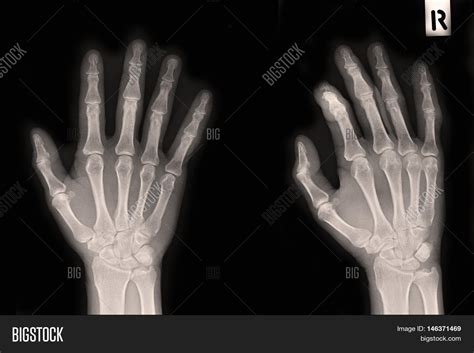

A broken finger, also known as a finger fracture, occurs when one or more of the bones in the finger are cracked or completely separated. This type of injury can happen due to various reasons, including:

The symptoms of a broken finger can vary depending on the severity of the fracture. Common signs include:

If you suspect a broken finger, it is essential to seek medical attention promptly. A healthcare professional will perform a physical examination and may order X-rays to confirm the diagnosis. Treatment options for a broken finger typically include: